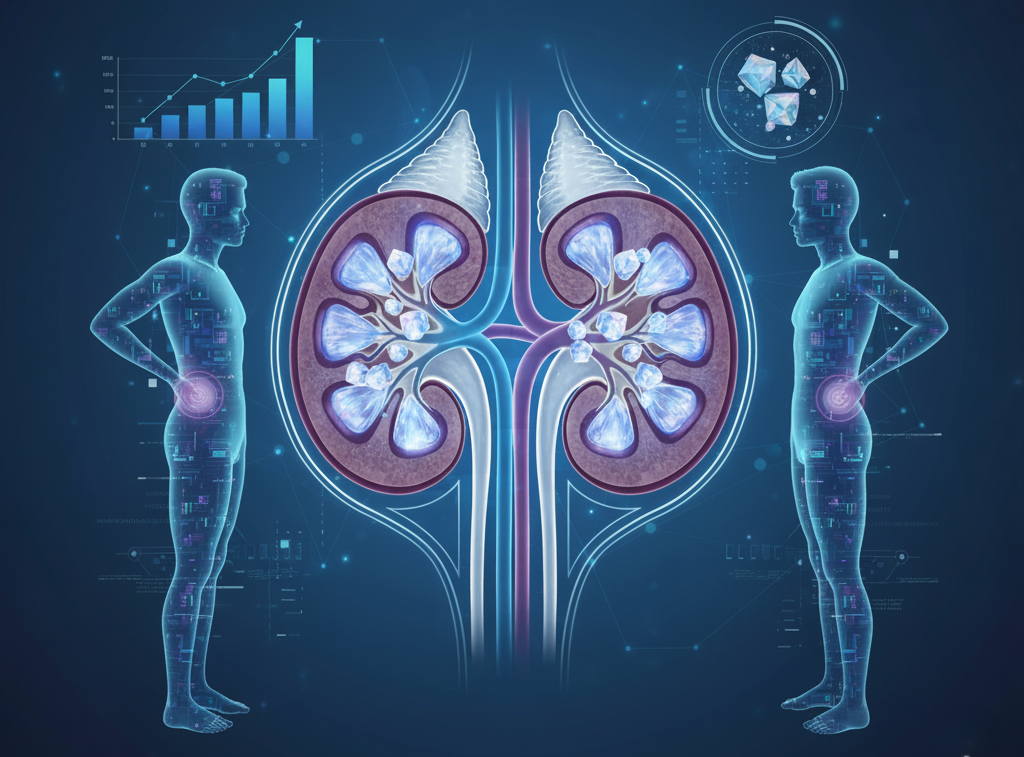

Kidney Stones in Young Adults For the Insights from Modern Medicine

No longer an older person's problem, kidney stones are being increasingly diagnosed among young people…